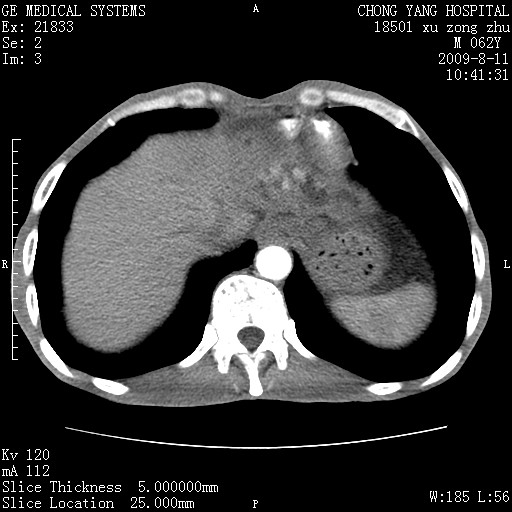

以下是引用杀毒软件在2009-8-11 16:35:00的发言:[br]肝内胆管扩张局限于左叶,胆管内有结石伴肝外胆管结石,胆管壁增厚呈弥漫性并发腹腔积液,胰腺边界模糊。[br][br]考虑---胆总管及肝内胆管结石继发胆管炎及胰腺炎,左肾下极囊肿,腹水。

以下是引用zjzjr在2009-8-11 17:35:00的发言:[br]肝内胆管扩张局限于左叶,胆管内有结石伴肝外胆管结石,胆管壁增厚呈弥漫性并发腹腔积液。[br][br]考虑---胆总管及肝内胆管结石继发胆管炎,左肾下极囊肿,腹水。